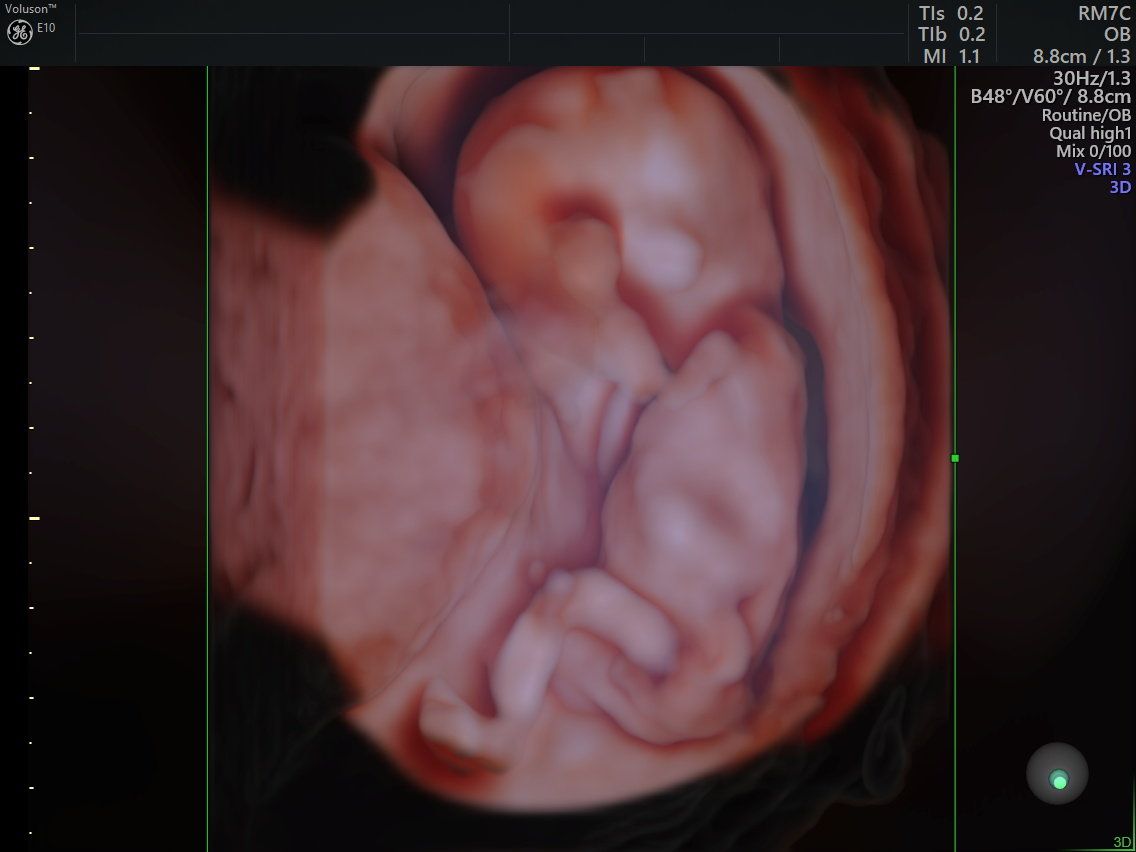

Da du fleißig wächst sind wir natürlich regelmäßig zum Arzt gegangen, um dich sehen zu können und um zu schauen, ob es dir gut geht. Hier warst du ca. 8 cm groß, 30 g schwer und ich in der 14. SSW schwanger. Zu dem Zeitpunkt haben wir auch schon allen in der Familie gesagt, dass du bald kommen wirst. ❤️